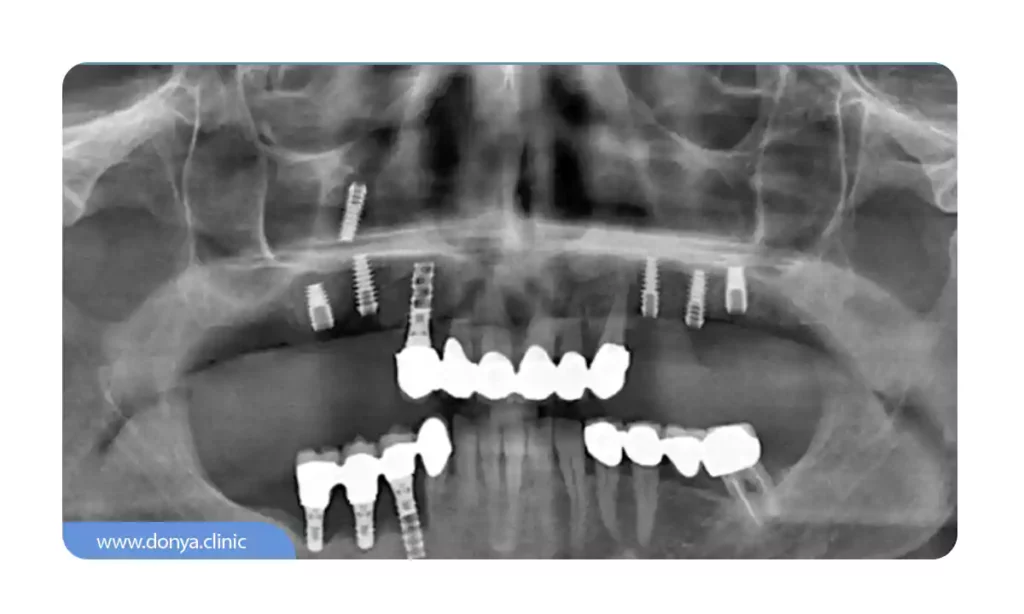

3. مشکلات سینوسی

عفونت سینوس می تواند یکی از عوارض ایمپلنت دندان باشد که در صورت بروز خطرناک خواهد بود. هنگامی که ایمپلنت در فک بالا قرار می گیرد، بسیار مهم است که به دیواره سینوسی که درست بالای استخوان فک بالا قرار دارد، آسیب نزند. برای درک بهتر، باید بدانید که حفره سینوس فضایی پر از هوا است که با یک دیواره و غشاء پوشانده شده است و هنگامی که ایمپلنت به داخل این فضا وارد شود یا آسیبی به آن بزند، باعث تحریک یا آسیب به غشاء شده و منجر به مشکلات سینوسی مانند احتقان، فشار یا درد شود.

اگر ایمپلنت خیلی نزدیک به حفره سینوس قرار گیرد یا وارد آن شود، می تواند خطر عفونت سینوس را نیز افزایش دهد زیرا هر باکتری که وارد محل کاشت می شود می تواند به طور بالقوه به حفره سینوسی نیز گسترش یابد و قطعا در این شرایط عفونت سینوس نیز رخ می دهد.

برای جلوگیری از بروز این مشکلات، دندانپزشک یا متخصص ایمپلنت شما قبل از قرار دادن ایمپلنت، آناتومی فک و سینوس را به دقت ارزیابی می کند. آنها ممکن است از تکنیک های تصویربرداری مانند اشعه ایکس یا سی تی اسکن برای تعیین بهترین محل کاشت ایمپلنت و اطمینان از بیرون زدگی آن به داخل حفره سینوس استفاده کنند.